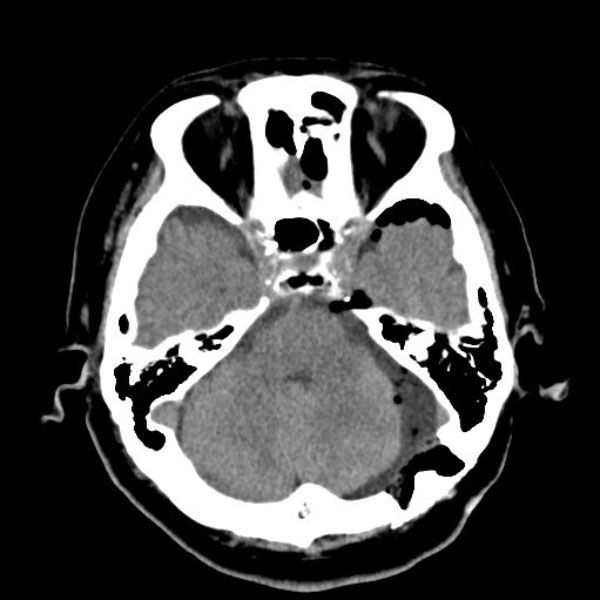

症例 '26年4月

No.

589

病名

'26年4月

70代

左三叉神経痛

減圧前